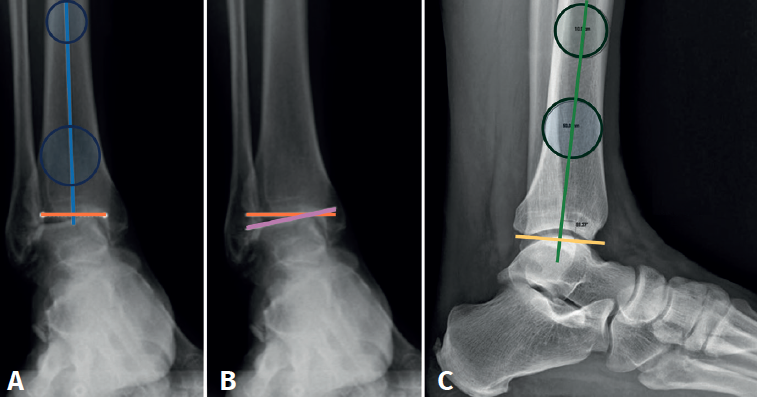

In the anterior ankle projection we evaluate the talar tilt or angle of inclination of the talus, which is increased in incongruent intra-articular injuries (Figure 1).

We must observe whether, in the lateral projections, there is an anterior translation of the talus, which often occurs in these chronic degenerative phenomena associated with instabilities (Figure 2).